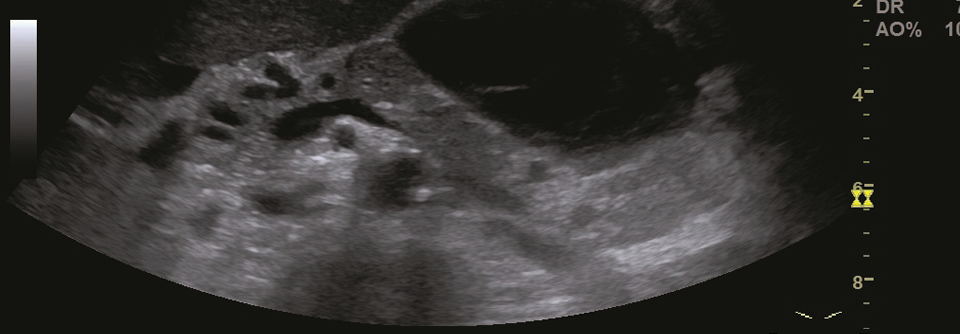

Bei einer 46-jährigen Frau wird eine akute Pankreatitis diagnostiziert. Die Patientin hat einen BMI von 35 und erhält wegen ihres erst kürzlich festgestellten Typ-2-Diabetes Metformin. Aufgrund von Wechseljahresbeschwerden wurde ihr zudem eine Hormonersatztherapie verschrieben, zur kardiovaskulären Primärprävention nimmt sie Statine. Zum Zeitpunkt der Pankreatitisdiagnose sind der Blutzucker mit 306 mg/dl und vor…